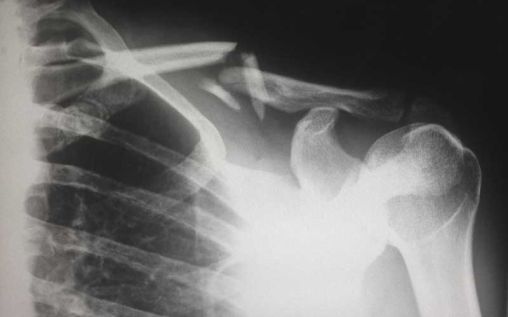

Fractures and broken bones

The human bone is very strong. It not only holds the body’s weight, but it also absorbs the impact of everyday movement, so that you can walk, run, and jump with ease. But that strength is nothing compared to the force of the impact of a car running at full speed. No matter how strong your bone is, a speeding metal box is definitely stronger. This is why bone injuries are common in pedestrian accidents. While common and very treatable, they’re nonetheless painful, bothersome, and even bring a lifetime of pain and suffering to the victims.

Fracture is a bone injury wherein the bone gets cracked and damaged from the impact. This requires weeks and even months to heal, limiting the mobility and function of the victim. If their work or daily routine require the use of their fractured limbs, then it means they may need to take a time-off to recover.

Broken bones, from the term itself, is easy to imagine. These are extremely painful and would definitely require more time to recover than fracture. Some instances require several operations to reattach the broken parts. The problem with both the fracture and broken bones is that even if they’ve successfully healed, there will be a lingering pain for the victims. It could range from simple discomfort, to prolonged pain that requires constant medication.